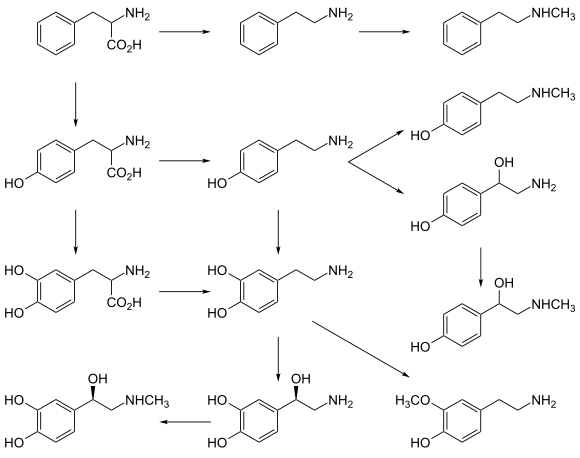

Neurotransmitters are generally synthesized in neurons and are made up of, or derived from, precursor molecules that are found abundantly in the cell. Classes of neurotransmitters include amino acids, monoamines, and peptides. Monoamines are synthesized by altering a single amino acid. For example, the precursor of serotonin is the amino acid tryptophan. Peptide transmitters, or neuropeptides, are protein transmitters that often are released together with other transmitters to have a modulatory effect.[3] Purine neurotransmitters, like ATP, are derived from nucleic acids. Other neurotransmitters are made up of metabolic products like nitric oxide and carbon monoxide.

- Norepinephrine is a member of the catecholamine classification of neurotransmitters. It is synthesized from the amino acid tyrosine. In the peripheral nervous system, one of the primary roles of norepinephrine is to stimulate the release of the stress hormone epinephrine (i.e. adrenaline) from the adrenal glands.[26]

- Epinephrine, a neurotransmitter and hormone is synthesized from tyrosine. It is released from the adrenal glands and plays a role in the fight-or-flight response. Epinephrine has vasoconstrictive effects, which promote increased heart rate, blood pressure, energy mobilization. Vasoconstriction influences metabolism by promoting the breakdown of glucose released into the bloodstream. Epinephrine also has bronchodilation effects, which is the relaxing of airways.[26]

- Catecholamines: dopamine (DA), norepinephrine (noradrenaline, NE), epinephrine (adrenaline)

Catecholamine and trace amine precursors

L-DOPA, a precursor of dopamine that crosses the blood–brain barrier, is used in the treatment of Parkinson's disease. For depressed patients where low activity of the neurotransmitter norepinephrine is implicated, there is only little evidence for benefit of neurotransmitter precursor administration. L-phenylalanine and L-tyrosine are both precursors for dopamine, norepinephrine, and epinephrine. These conversions require vitamin B6, vitamin C, and S-adenosylmethionine. A few studies suggest potential antidepressant effects of L-phenylalanine and L-tyrosine, but there is much room for further research in this area.[70]